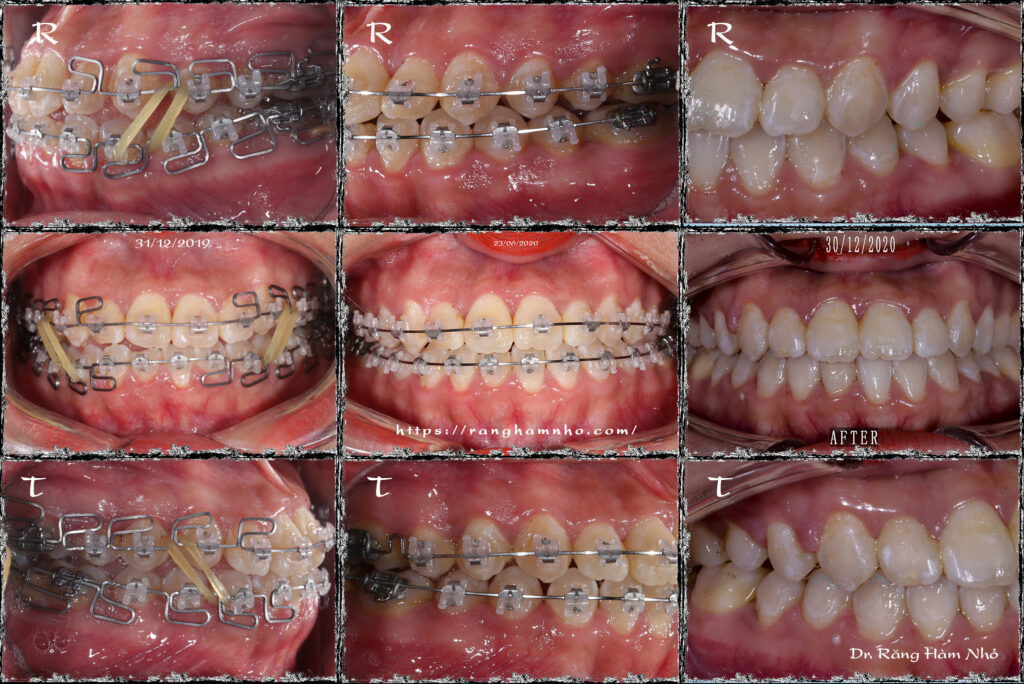

Một case sai khớp cắn hạng III góc đóng, với chen chúc cắn kéo nhiều răng. Giai đoạn san bằng và sắp đều đã được hoàn thiện trước đó. Dr Răng Hàm Nhỏ tiếp nhận và bẻ MEAW trên dây TMA 17×25 kết hợp thun 1/4 hạng III ngắn 6.5Oz trong 6 tháng. Giải quyết được hở khớp vùng răng hàm, lồng khớp hai hàm về tối ưu. Tinh chỉnh khớp cắn, duy trì và tháo niềng.

Kết quả so sánh phim chụp trước và sau điều trị.

Bệnh nhân hoàn toàn hết khuôn mặt lõm cắn ngược, nụ cười thay đổi như thành một người khác